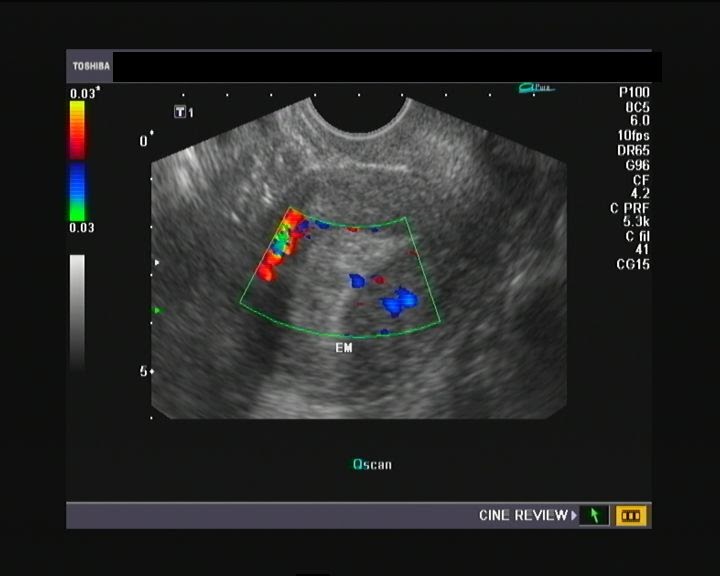

nabothian cyst in cervix II Dr Nasrin Fatema II Realtime Ultrasound II nabothian cyst in TVS

Ultrasound and Color Doppler videos Multiple Nabothian cysts of the cervix

CISTO DE NABOTH NO COLO DO ÚTERO PELO ULTRASSOM TRANSVAGINAL Saiba aqui o SIGNIFICADO! YouTube

Quistes de Naboth Ecografía